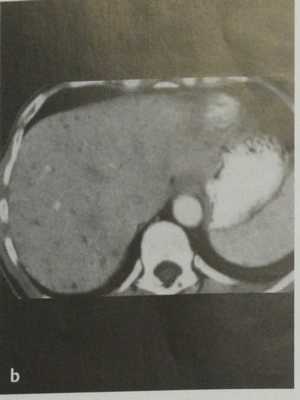

(Левый) Серошкальный ультразвуковой срез печени. Отмечается неоднородность эхоструктуры паренхимы печени, вызванная множественными гамартомами печени, слишком маленькими для того, чтобы их выделить. Другие мелкие, кистозные образования представляют собой гамартомы чуть большего размера, внутреннее кистозное строение которых может быть визуализировано.

(Правый) Цветовая допплерография подтверждает, что у этого пациента с множественными гамартомами печени отсутствует васкуляризация их кистозного содержимого. (Левый) КТ с контрастированием у этого же пациента, аксиальная проекция. Визуализируются множественные крошечные гамартомы печени низкой плотности, хаотично расположенные по всей паренхиме печени.

(Слева) На аксиальной КТ с контрастным усилением у женщины 76 лет с верифицированным раком почки визуализируются множественные мелкие гиподенсные очаги, диффузно распределенные в печени. Обратите внимание также на клипсы после нефрэктомии. Билиарные гамартомы в этом случае не следует ошибочно принимать за метастазы.

(Справа) На аксиальной КТ у этой же пациентки определяется большее количество очагов, которые - в чем практически уже нельзя усомниться - представляют собой билиарные гамартомы. Очаги остаются стабильными на протяжении многих лет, при этом иммунный статус пациентки не нарушен.

a) УЗИ. Негомогенное изображение с мелкими трудноопределяемыми гипоэхогенными очагами.

b) КТ после введения контраста. Множественные мелкие очаги пониженной плотности, не накапливающие контраст.

c) МРТ после введения контраста. Множественные мелкие гипоинтенсивные очаги, не накапливающие контраст.

d) МР-изображение в режиме НАSТЕ. Множественные гиперинтенсивные очаги с кистозным компонентом.